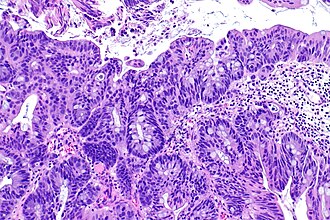

Adenocarcinoma of the urinary bladder. H&E stain. | |

| LM | nuclear pleomorphism (may be mild), usually glandular differentiation (most common), no urothelial differentiation - essential |

- Nuclear pleomorphism - may be mild.

- Usually glandular differentiation (most common).

- Frequently looks just like colorectal adenocarcinoma.

- Without urothelial differentiation - essential.[3]

- +/-Evidence of invasion such as:

- Desmoplastic stroma.

- Extensive disordered or cribriform growth.